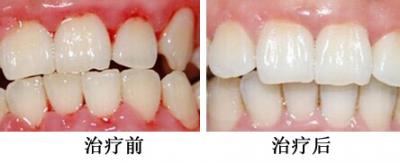

正畸案例1

正畸案例1